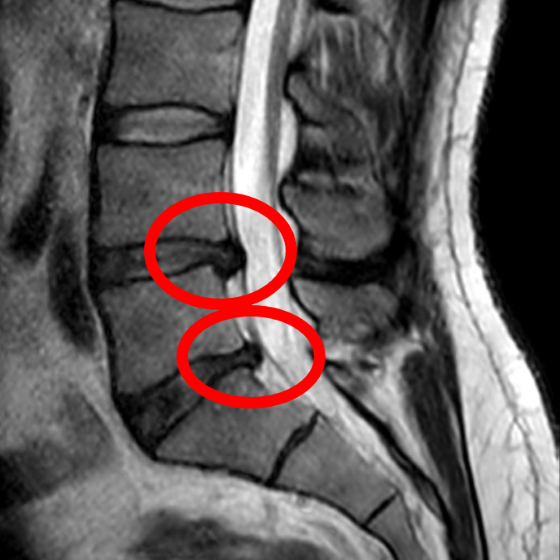

Badanie za pomocą rezonansu magnetycznego jest szczególnie cenne dla szczegółowego obrazowania mózgu i rdzenia kręgowego, Źródło: www.nobelprize.org